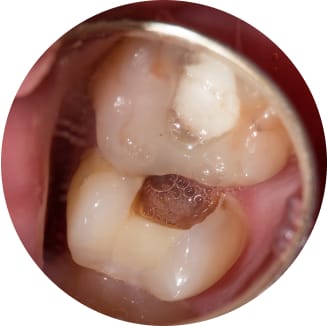

深い虫歯・根管治療

深く神経にまで進行したむし歯も丁寧に歯内療法を行っており、マイクロスコープも導入しています。